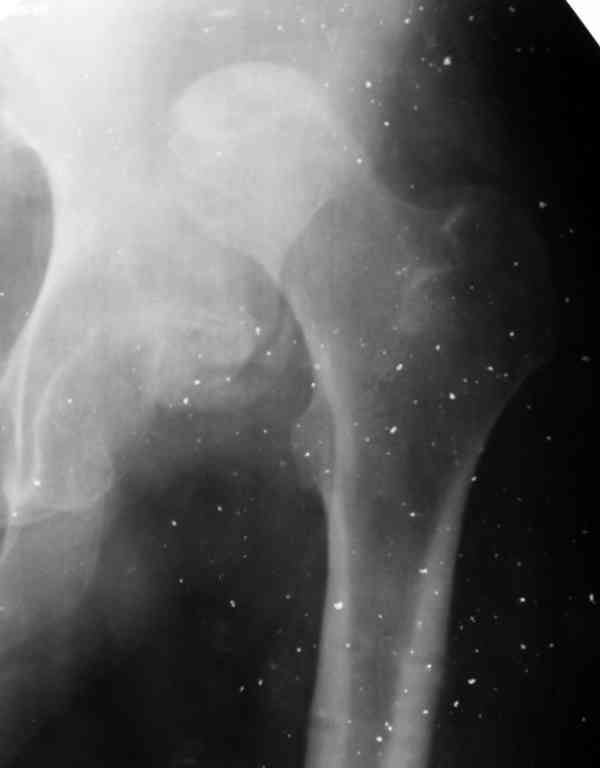

Слайд 1

Слайд 2

Слайд 3

Слайд 4

Devushka predstavlennaya na snimke nachala s LLD 9 cm, valgus deformation of the tibia, huge Trendelenburg( vidno na snimke).

Seichas : no LLD ,no Trendelenburg, reasonable hip motion.A samoe glavnoe ei ne predstoit kaghdye 10-15 let delat revision THR.